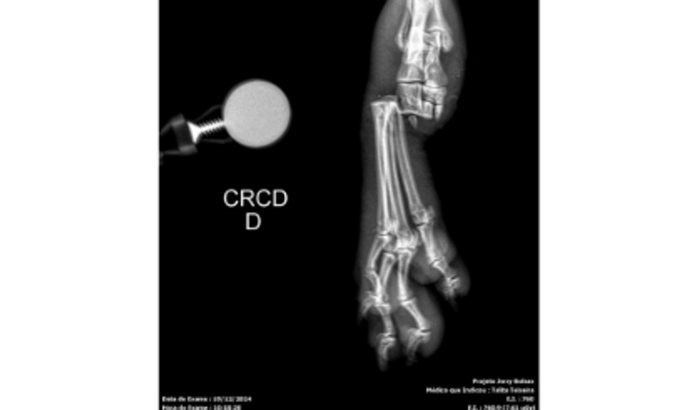

Hoje venho com o coração apertado pedir ajuda para o meu fiel companheiro, o Udi, um poodle de 14 anos que sempre foi uma fonte de amor e alegria na minha vida. Infelizmente, ele foi vítima de uma crueldade inimaginável: alguém, sem motivo, o agrediu com um pedaço de madeira na rua, quebrando o osso da sua pata ao meio.

O estado da pata é muito grave, e os veterinários alertaram que, sem a cirurgia, o Udi corre o risco de perder a pata. É uma situação urgente, e o valor do procedimento está além do que eu consigo pagar sozinho. Por isso, venho pedir a ajuda de vocês para salvar o Udi.